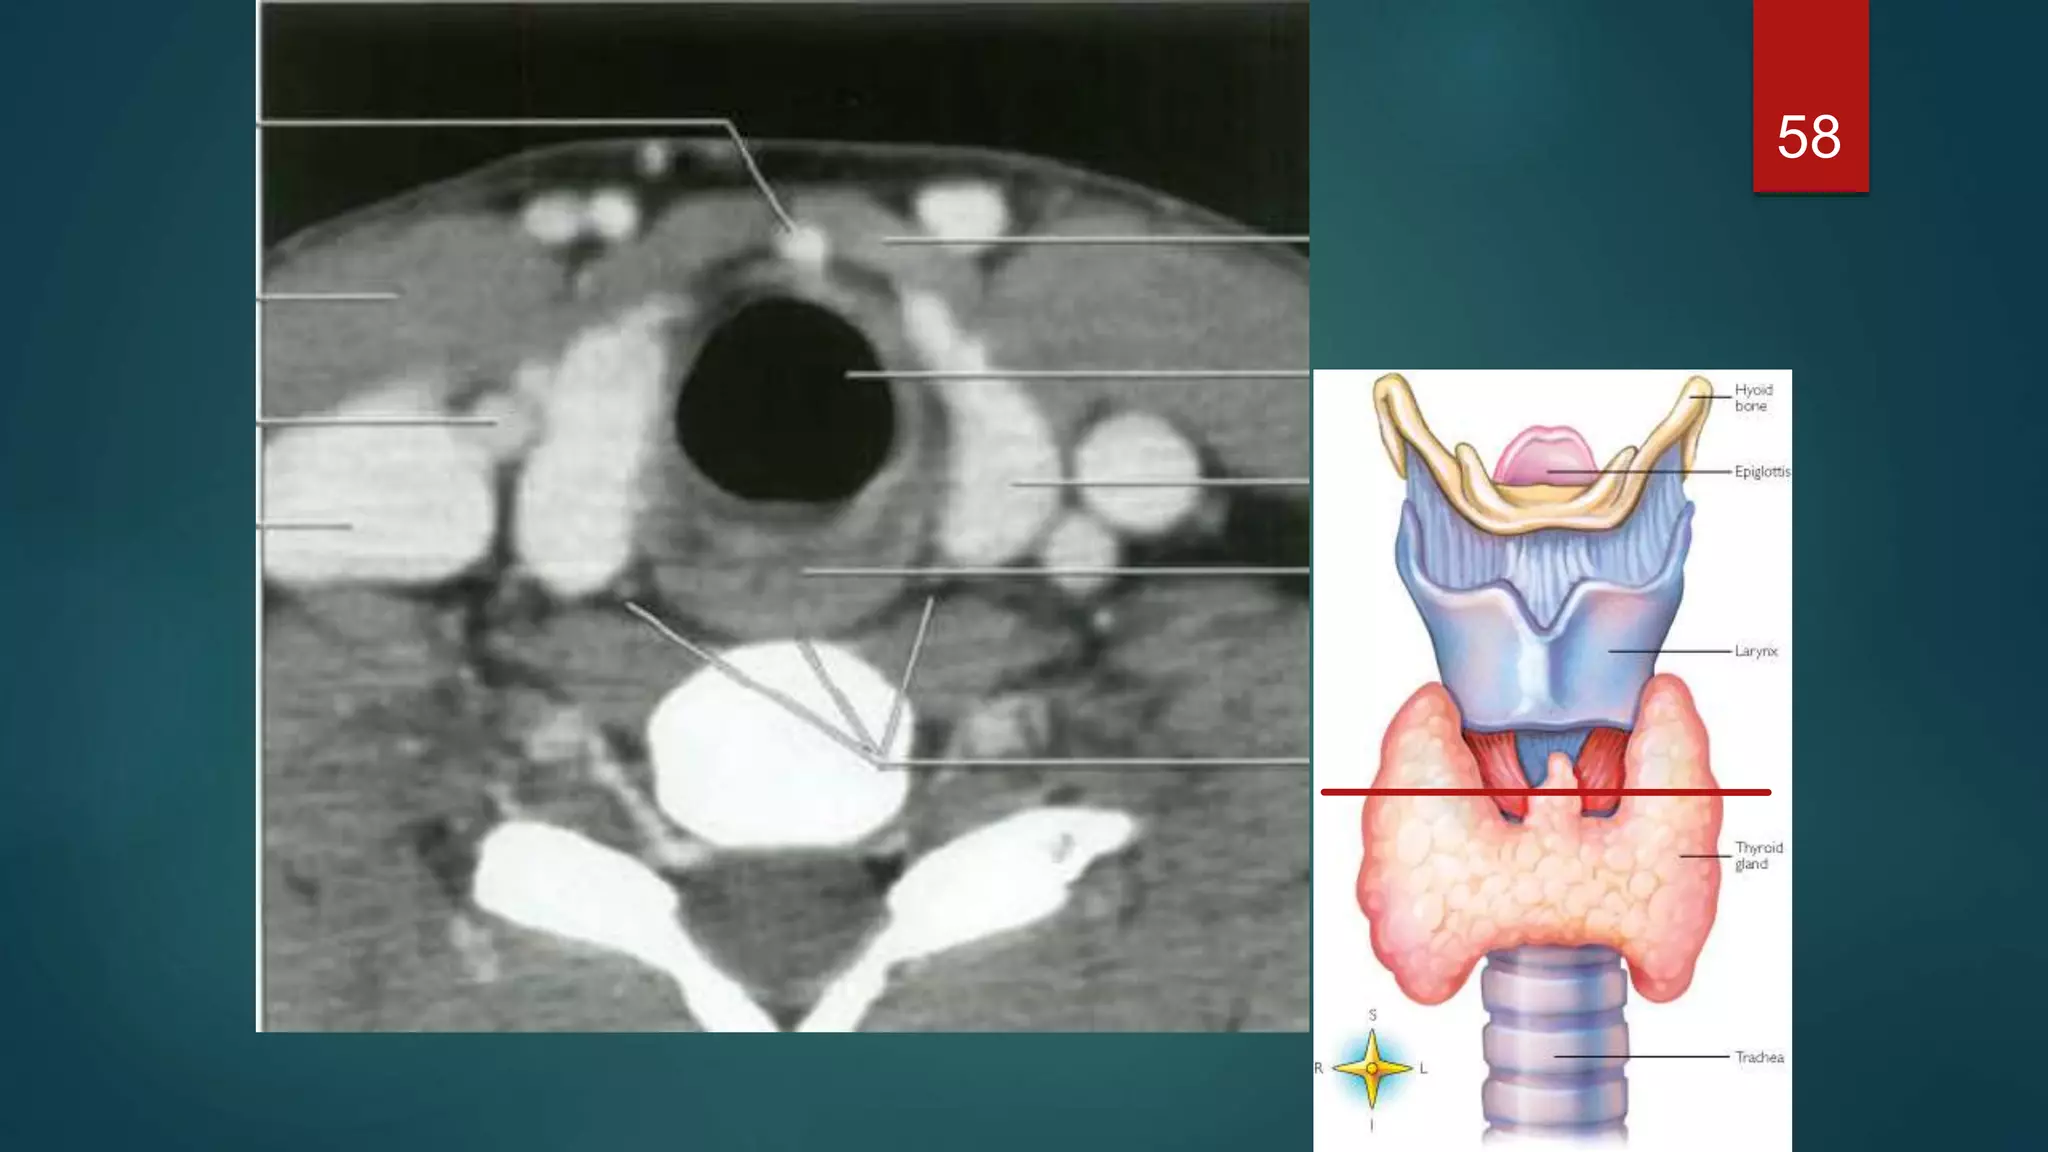

 The thyroid gland consists of two lateral lobes joined by a midline isthmus, and

lies anterior and lateral to the trachea.

 The lobes extend from the thyroid cartilage superiorly to the sixth tracheal ring

inferiorly

 Posterolaterally are the neck vessels, Behind these, on either side, are the

prevertebral muscles

 Anterior to the gland are the strap muscles of the neck and the sternomastoid

muscles

58